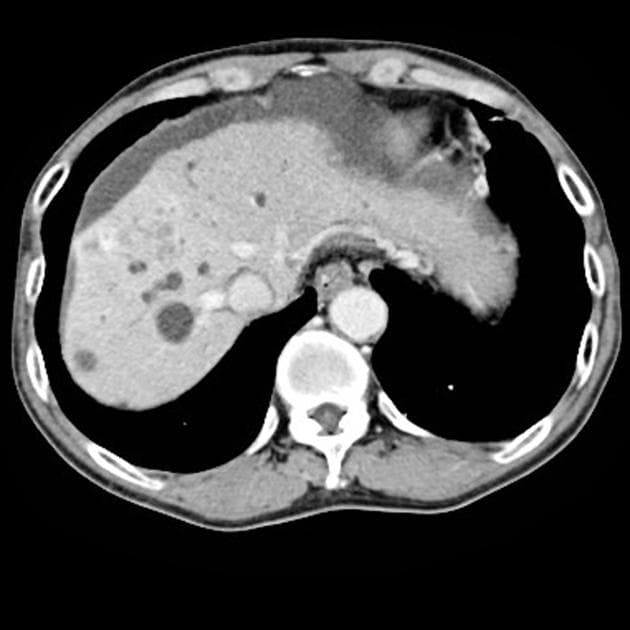

- Chụp cắt lớp ngang T2WI: thấy các ống mật trung tâm giãn khu trú, kết thúc tại một khối giảm tín hiệu ở vị trí nối các ống mật gan chính.

- T1 FS: tổn thương giảm tỷ trọng ở trung tâm, tại/gần cửa gan (porta hepatis). Không thấy tăng quang đáng kể sau tiêm thuốc cản quang.

Ung thư ống mật tế bào gan vùng cửa gan (hilar cholangiocarcinoma – u Klatskin) (hilar cholangiocarcinoma - Klatskin tumor).

Ung thư ống mật tế bào gan vùng cửa gan, còn gọi là u Klatskin, là khối u ác tính xuất phát từ biểu mô của các ống mật gần, đặc biệt tại vị trí nối ống mật gan phải và trái. Bệnh thường khởi phát âm thầm với các triệu chứng không đặc hiệu như vàng da, ngứa, sụt cân, gây khó khăn trong chẩn đoán. Trên hình ảnh, tổn thương điển hình là khối u vùng cửa gan gây giãn ống mật theo phân thùy, với dấu hiệu 'cắt cụt' trên chụp đường mật. MRCP rất nhạy trong việc xác định mức độ và phạm vi tắc mật. Trên MRI có tiêm thuốc, khối u thường giảm tín hiệu và tăng quang kém trên các dãy T1 và T2. Việc phân biệt với các đoạn hẹp lành tính, đặc biệt trong viêm đường mật xơ hóa tiên phát, có thể khó khăn và cần sinh thiết hoặc đánh giá nội soi. Chẩn đoán sớm rất quan trọng để xem xét cắt bỏ phẫu thuật hoặc ghép gan, mặc dù phần lớn các trường hợp khi chẩn đoán đã không còn khả năng cắt bỏ.